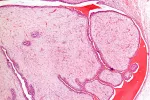

La mastopatía fibroquística de la mama también se denomina adenosis, displasia mamaria o condición fibroquística. Es un conjunto de alteraciones naturales del contenido de las mamas; la causa son los ciclos hormonales que existen a lo largo de la vida de la mujer. No se considera una enfermedad, solo son cambios de la mama que no predisponen al cáncer.

La mujer no está en edad fértil, no hay lesiones nuevas y las anteriores evolucionan. Las induraciones forman quistes únicos y, en general, las lesiones ya no tienen por qué ser bilaterales.